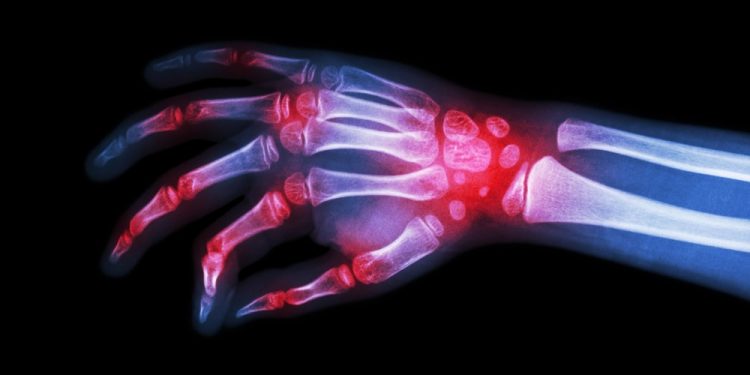

Rheumatoid arthritis — or RA for short — is a chronic inflammatory disease that affects joints, especially in the hands and feet, but it can affect more than just the joints. For some people, RA leads to damage to other systems in the body, including the skin, eyes, heart and blood vessels. It is caused by one’s immune system mistakenly attacking the body’s own tissue. There is no cure for RA, but it can be treated to minimize the effects, however physical disabilities can still arise from severe cases of RA.

Typical symptoms that indicate one may have RA include tender and swollen joints, joint stiffness, fatigue, fever and weight loss. In terms of the joint stiffness, it is usually worse upon waking up in the morning or following periods of inactivity. RA often begins in smaller joints, then as it gets worse it spreads to other areas, including the wrists, ankles, hips and shoulders. About 40 percent of RA patients also have symptoms that don’t affect the joints, with those structures including the lungs, heart, kidneys and bone marrow.

The symptoms vary in severity between patients, but it is important to notice the signs early to start treatment quickly because over time — and especially without treatment being performed — RA can cause joints to become deformed and shift out of place. If you notice swelling in your joints, you should make an appointment to see your doctor to get a professional opinion about whether it is actually caused by RA.